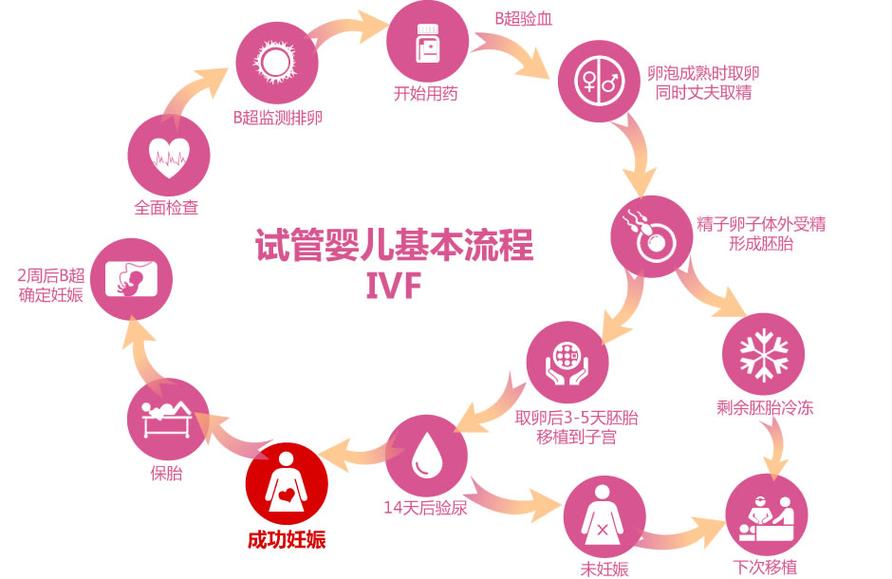

说起试管婴儿,很多人会想到“高科技”、“昂贵”等词,但很少有人会想到“失败”。然而,试管婴儿胚胎培养的失败是真实存在的,它给许多家庭带来了沉重的心理和经济负担。今天,我们就来谈谈试管婴儿胚胎培养失败的原因及其解决方案。

母体因素也是导致胚胎培养失败的重要原因。根据《生殖医学杂志》2023年的统计,约有20%的试管婴儿失败是因为母体因素。这些因素包括子宫内膜异常、内分泌失调等。

操作技术问题也不容忽视。据《生殖医学进展》2024年的数据显示,约有10%的试管婴儿失败是因为操作技术问题。包括胚胎移植技术、实验室培养环境等。

1. 提高胚胎质量

- 优化促排卵方案,提高卵子质量

- 采用ICSI技术,提高受精率

- 采用胚胎基因诊断技术,筛选健康胚胎

- 调整内分泌,改善子宫内膜环境

- 治疗子宫内膜异常,提高着床率

- 引进先进的胚胎培养设备,提高实验室培养环境

- 加强技术培训,提高胚胎移植技术水平